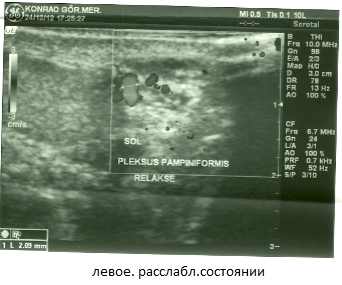

Мужу сделали УЗИ. Доктор сказал, что у мужа двустороннее варикоцеле. Нужна операция. Вот результаты УЗИ:

Заметно расширены вены левого гроздевидного сплетения и извилистость. Максимальный диаметр вен в расслабленном состоянии 2.09 мм., при проведении пробы Вальсальве 3,50 мм. В положении лежа при проведении пробы Вальсальве количественное увеличение венозных структур, увеличение диаметра до патологического размера. В режиме ЦДК, при проведении пробы Вальсальве был выявлен кровоток в обратном направлении - рефлюкс .

Фото тоже я прикрепила